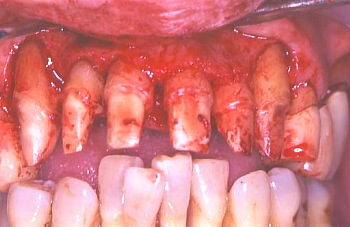

⑥ 骨が異常に減退しているので歯冠が長く見える。また歯の根っこの表面に歯石が見られ、これが存在する限り、歯周病はよくならないのでこれを取り除くのも一つの大きな外科の目的である。○印で示しているのは歯周ポケットの中で歯根面に付着していた歯石である。

⑦ この写真でも骨が異常に減退した長い歯冠とその歯の根っこの表面に歯石が見られる。○印で示しているのは歯周ポケットの中で歯根面に付着している歯石。

⑧ 歯根に付着していた歯石を除去した。もう一つの大きな外科手術の目的は歯周骨が細菌作用により、デコボコになった骨の表面部分を滑らかに整える事である。

⑨ 歯周外科により、歯根面全体と骨表面がきれいに清掃、整えられた。